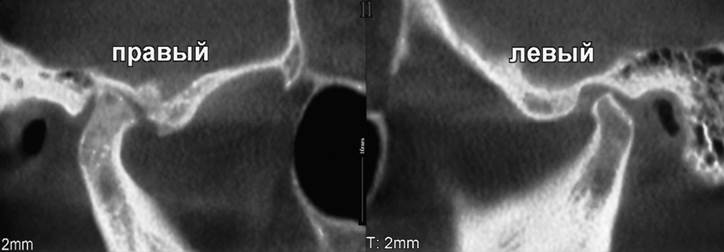

Проведение рентгенографии позволяет определить вид артроза. При склерозирующей патологии суставная щель сужается, повышается плотность костных структур. Для деформирующего артроза характерно изменение формы сустава, уплощение суставной ямки и образование остеофитов.

- рентгенография для определения состояния суставной щели, количества образовавшихся остеофитов, обнаружения обызвествленных участков;

- компьютерная томография для установления воспаления в мягких тканях и оценки состояния связочно-сухожильного аппарата.